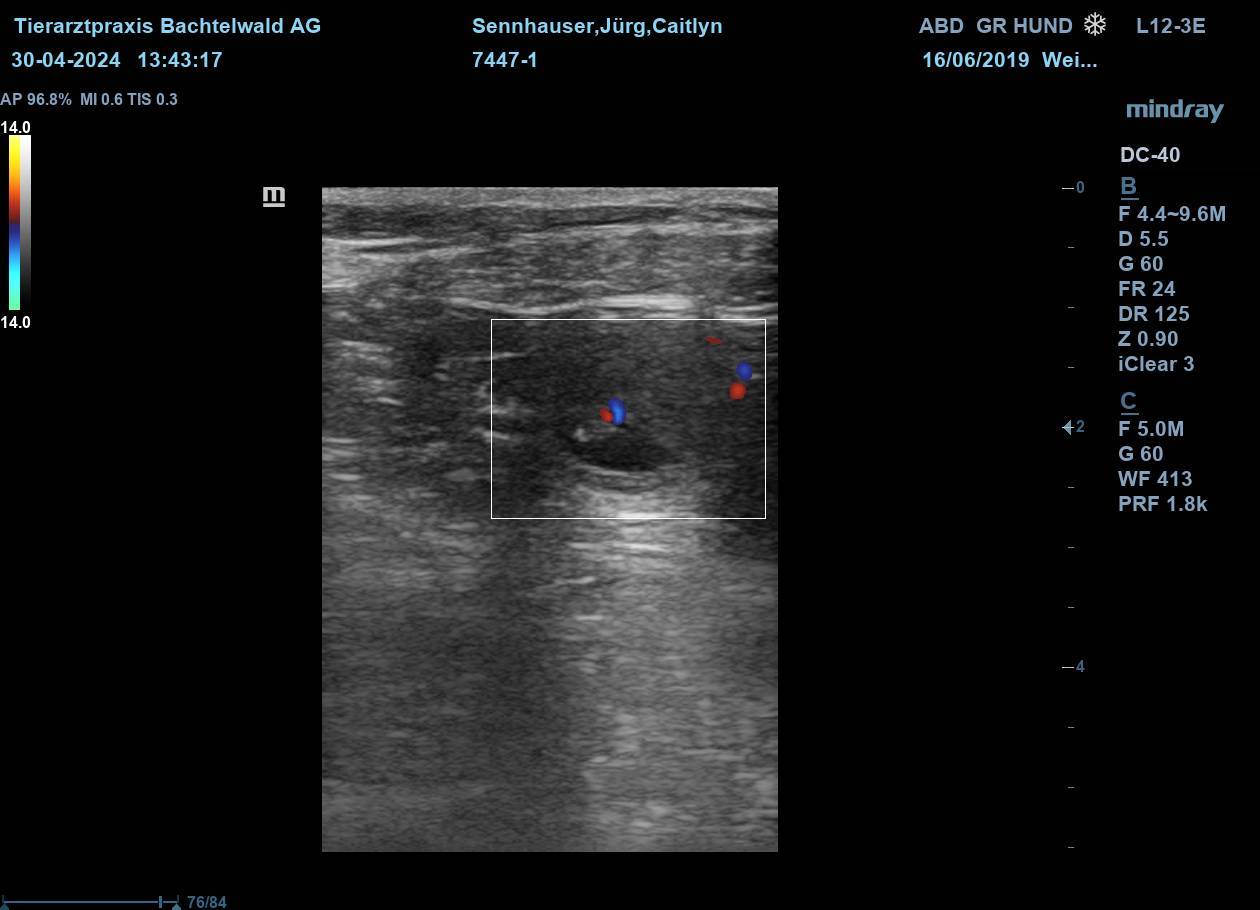

Caitlyn wurde Anfang April mit dem Xanadu "Zane" verpaart.

Nun heisst es "gespannt warten" bis wir in 3 Wochen den Ultraschall machen werden.